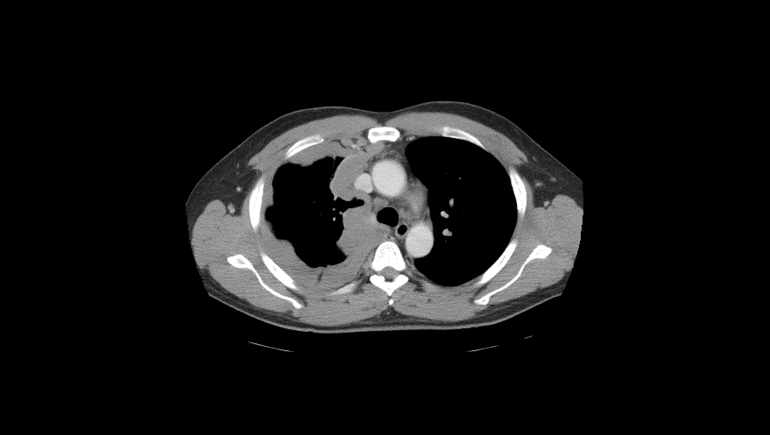

Example scan of a patient presenting with mesothelioma